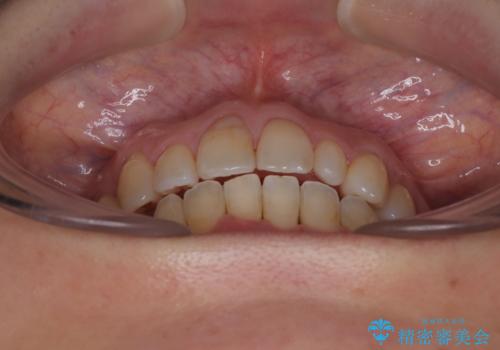

予想通り左側の咬み合わせの調整に苦労をしましたが、最終的には違和感のない咬み合わせを達成することができました。